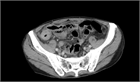

1. 画像検査のみでは腸結核の診断は困難であるが、他の腹腔内疾患との鑑別、内視鏡の適応、緊急性のある病態の有無の評価のため、状況によっては行う価値があると考えられる(推奨度2)